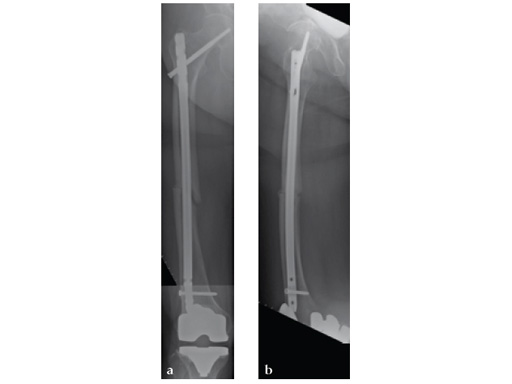

Patient was allowed and achieved immediate weight bearing and in 6 weeks callus is seen at the fracture site (see Fig 7a-b).